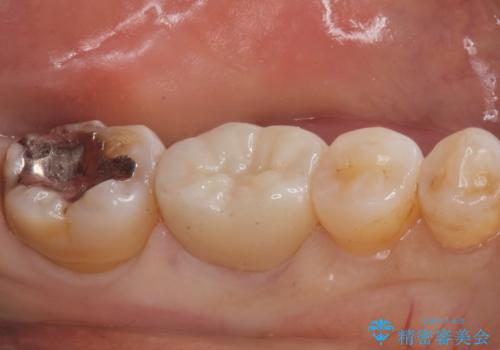

割れるリスクの少ないジルコニアクラウンにて治療しました。

- ジルコニアクラウン・仮歯 12.1万円費用は治療当時の料金となります

白い被せ物が入り、とても満足して頂けました。

現在銀の詰め物、被せ物のやりかえを検討しているそうです。